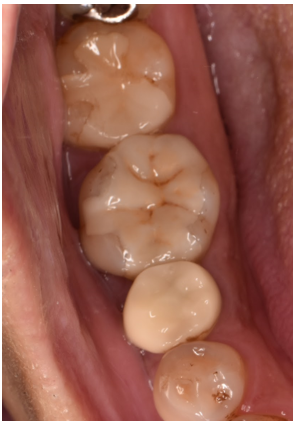

治療前

治療後

| 行ったご提案・治療内容 | 透明感のある白で目立たず、ちょうどよい強度のあるE-maxをご提案しました。 |

| 術後の経過・現在の様子 | 自然な白さで噛み合わせも問題ないとご満足いただけました。 |